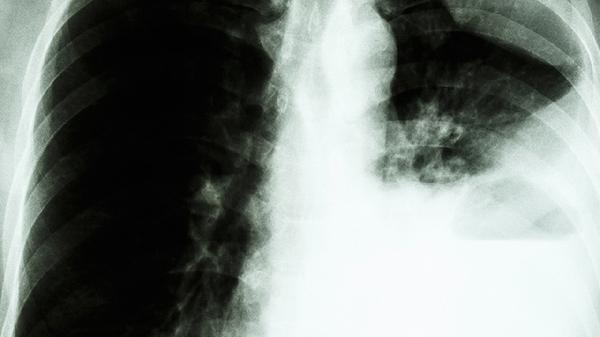

肺部炎症通常需遵医嘱使用阿莫西林胶囊、头孢呋辛酯片、左氧氟沙星片、阿奇霉素分散片、盐酸莫西沙星片等消炎药。肺部炎症可能与细菌感染、病毒感染、支原体感染等因素有关,建议及时就医明确病因后针对性用药。